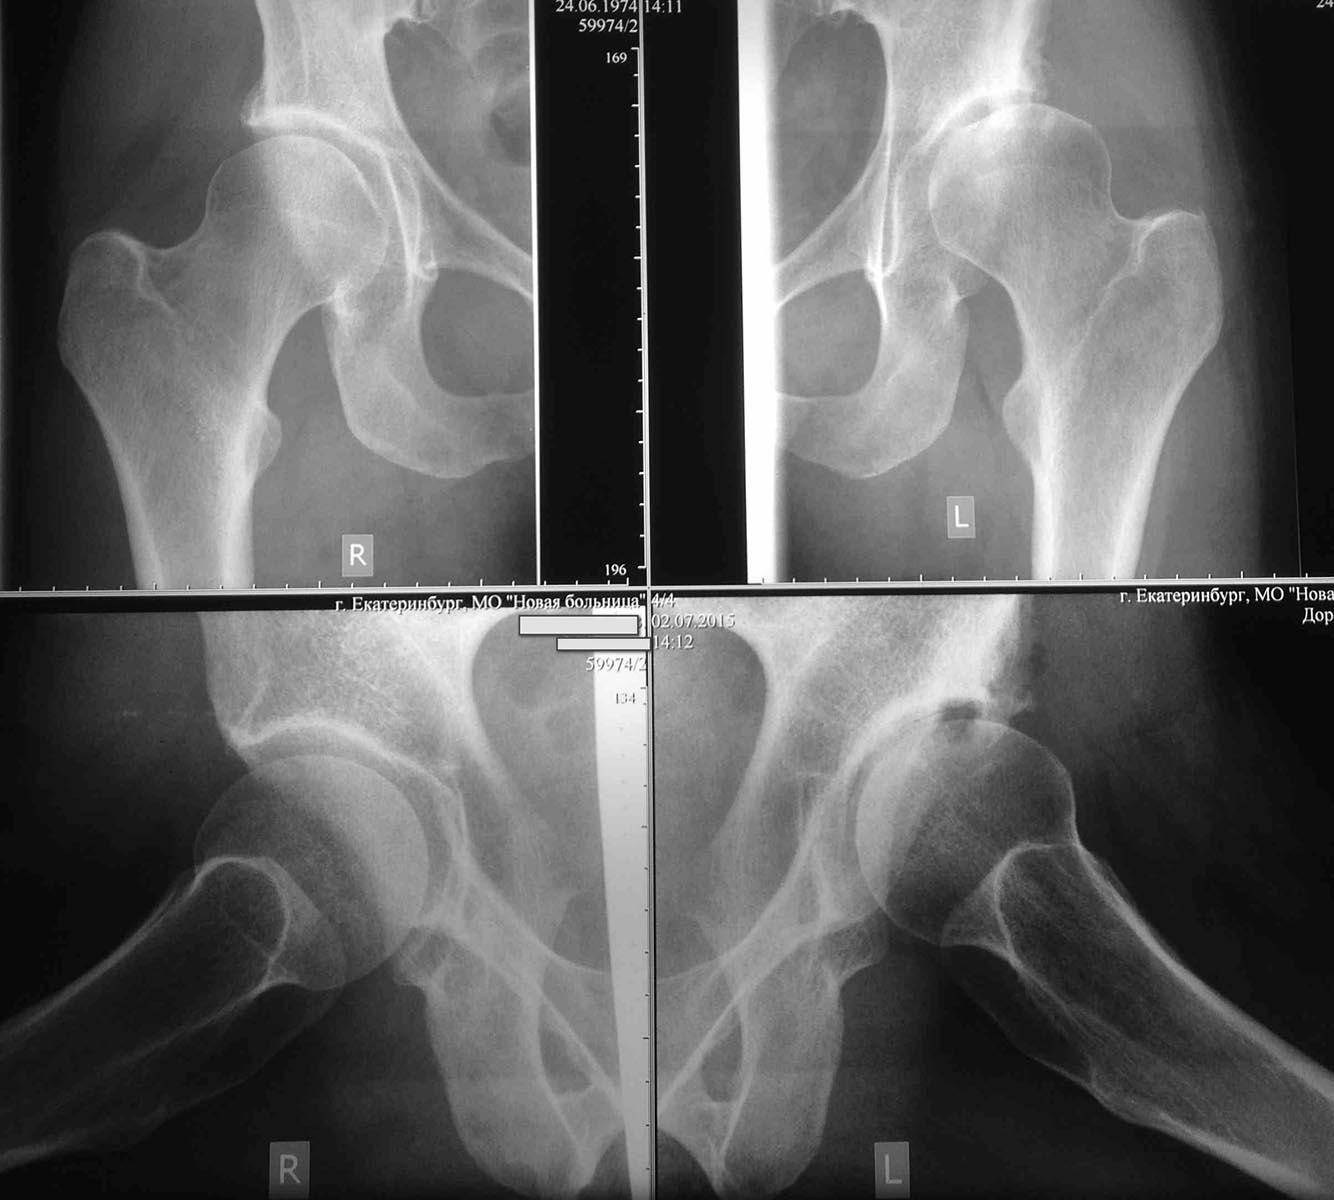

Обратилась молодая приятная женщина 41 года с диспластическим коксартрозом.

Беспокоит боль в левом тазобедренном суставе при движениях. Везде, где

она консультировалась однозначно предлагали эндопротезирование. На мой

взгляд за сустав еще можно побороться. Возьмет кто-нибудь на ПАО? лучше